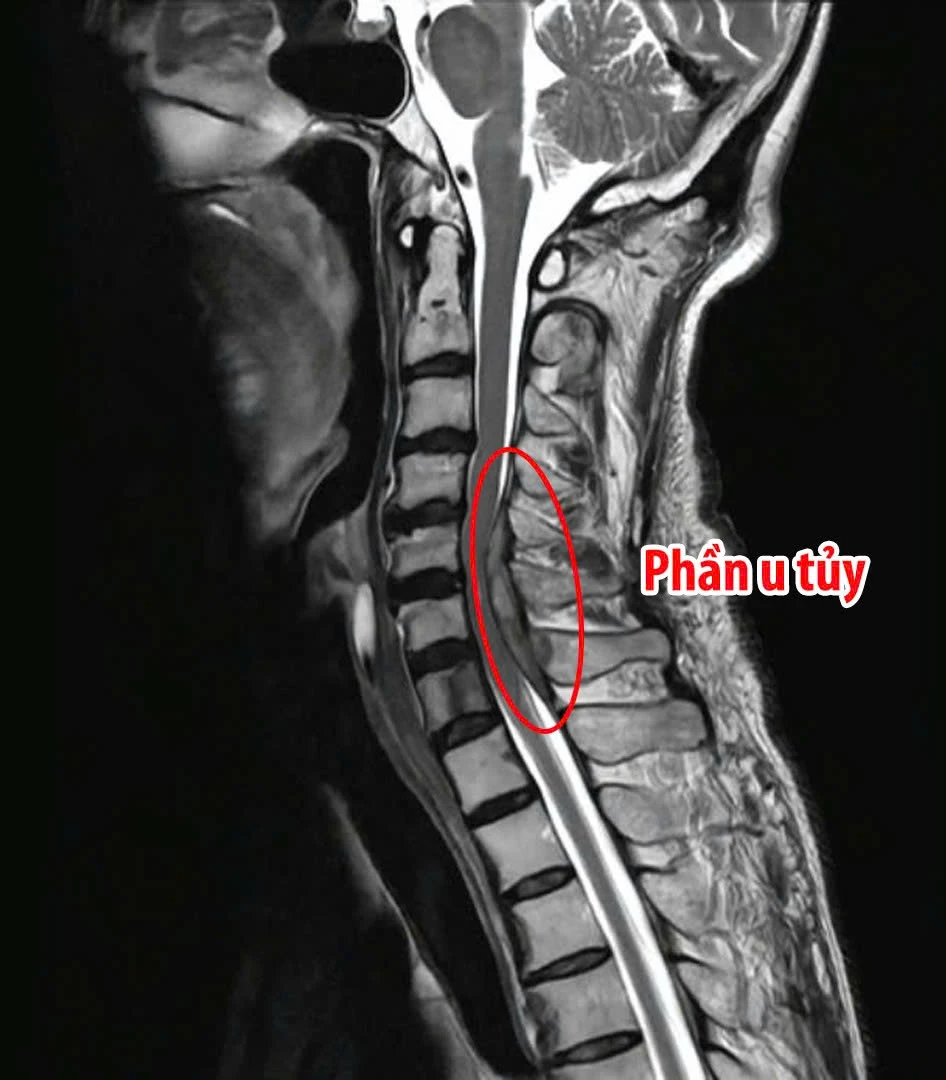

Theo đó, bệnh nhân V. vào bệnh viện trong tình trạng yếu liệt tứ chi, bí đại tiểu tiện, đau nhiều vùng cổ lan xuống hai tay. Kết quả thăm khám cho thấy sức cơ tứ chi chỉ còn 2/5, gần như mất khả năng vận động. Hình ảnh chụp cộng hưởng từ (MRI) xác định khối u tủy tại đoạn cột sống cổ 5 và 7 gây chèn ép nặng, biến dạng tủy sống kèm phù tủy - một tổn thương nguy hiểm có nguy cơ dẫn đến liệt. Trước tình trạng nguy kịch của bệnh nhân, ê-kíp y, bác sĩ Khoa Ngoại Thần kinh - Cột sống của bệnh viện đã tiến hành hội chẩn và quyết định phẫu thuật giải ép tủy, lấy trọn khối u kết hợp cố định cột sống cổ bằng đường mổ sau. Đây là kỹ thuật chuyên sâu, đòi hỏi sự chính xác cao nhằm loại bỏ tổn thương nhưng vẫn bảo tồn tối đa chức năng tủy sống và hệ thần kinh.